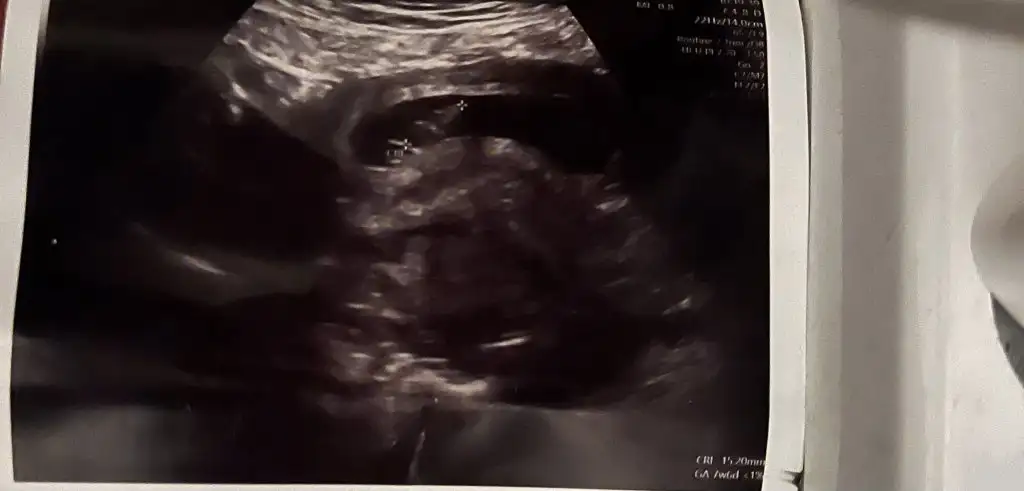

Rica edersem benimkinde bakar mısın lütfen 11 ve 9 haftalık resimler